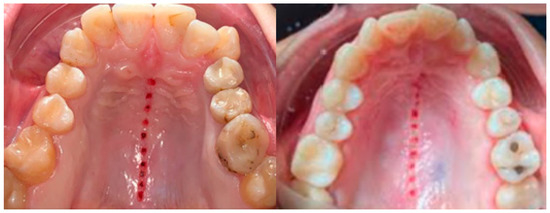

- MARPE associated with cortico-puncture therapy efficiently split the midpalatal suture in adults. The mean split at the anterior nasal spine (ANS) and posterior nasal spine (PNS) was 3.76 and 3.12 mm, respectively. The magnitude of the split at the PNS was smaller than at the ANS (by approximately 85% of the distance), showing that the opening of the midpalatal suture was almost parallel in the anteroposterior direction.

- MARPE therapy associated with cortico-puncture therapy had a positive outcome on midpalatal suture opening and maxillary advancement, but a medium molar inclination of 2.005° was also observed, suggesting that tooth movement cannot be avoided because of the anchorage of the MARPE device at the molar level.

- Our results suggest that non-surgical palatal expansion, assisted by micro-implants and cortico-puncture, is achievable and predictable in young adults. This occurs in safe conditions without the need for more complex surgical treatment.

- The combination of MARPE and the cortico-puncture method proved to be a non-surgical treatment option to correct maxillary transverse deficiency in young adult patients. Cortico-puncture was able to weaken the suture interdigitation, thus facilitating the split.